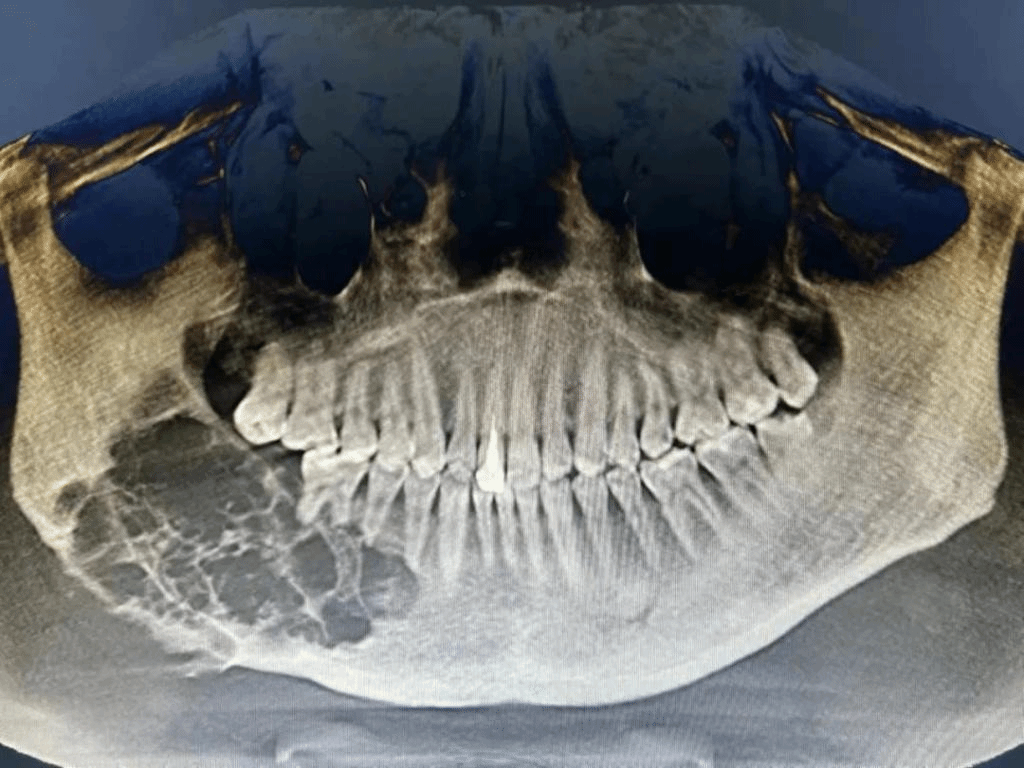

肿瘤诊断影像(左)肿瘤切除并移植后(右)

31岁的李先生于7个月前检查出右侧下颌骨巨大成釉细胞瘤,新疆医科大学口腔医(学)院口腔颌面肿瘤外科龚忠诚教授团队为他实施了右侧下颌骨扩大切除手术,利用数字化外科技术将患者小腿腓骨移植至右侧下颌骨,实现下颌骨的精确修复,成功恢复了下颌骨和面部外形。